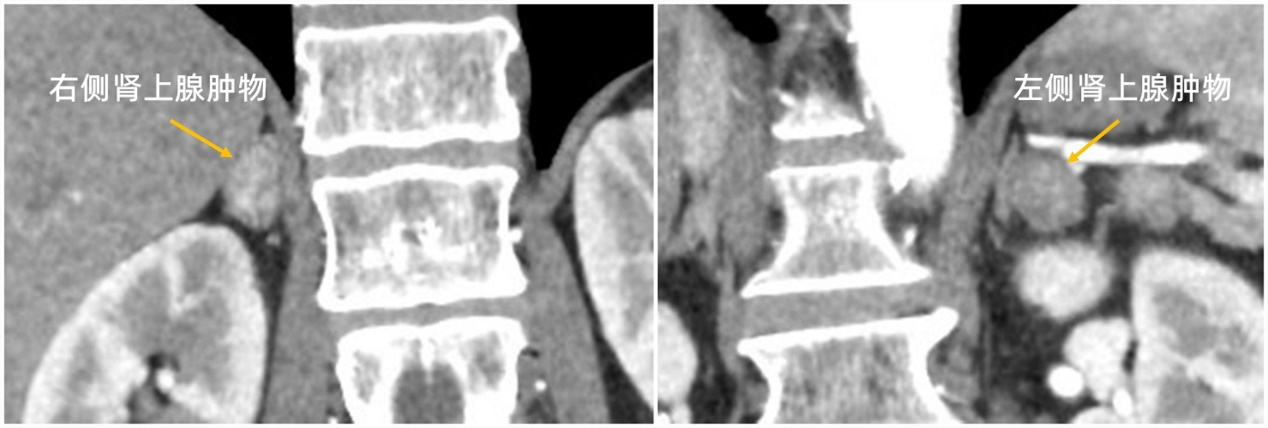

60岁男性患者,肢体无力急诊就诊,发现血钾2.37mmol/L(正常范围3.5-5.5mmol/L),为严重低钾血症。内分泌科内分泌代谢团队,根据其典型高血压、低血钾、双侧肾上腺肿物症状结合血液筛查指标静脉血醛固酮浓度/肾素浓度ARR值585(正常值<30),诊断原发性醛固酮增多症(简称原醛症)、醛固酮瘤明确。对于双侧肾上腺肿物考虑醛固酮瘤患者,开展左右两侧肾上腺静脉分别单独取血,通过血液样本检查确定醛固酮分泌优势侧,是制定手术切除方案的关键。为此,血管外科与内分泌科密切协作,在吴巍巍院长助理兼血管外科主任的指导下,血管外科张童副主任医师和杨宇主治医师利用微创腔内技术,将微导管分别精确选入左侧及右侧肾上腺静脉,成功获得分侧肾上腺静脉血样,进而根据其激素含量,明确醛固酮分泌优势侧。1周后泌尿外科张刚主任医师、肖博副主任医师行腹腔镜手术,顺利切除左侧肾上腺肿物,大小约2×1.0cm,圆球形,黄色,术后病理回报肾上腺皮质腺瘤。患者血钾纠正、血压控制良好。三科精诚协作,完成对双侧肾上腺肿物的精确诊断,实现醛固酮瘤患者的精准医疗。

原醛症在我国难治性高血压患者中的检出率为7.1%,是不可忽视的高血压病因。肾上腺静脉取血术是公认的原醛症分型诊断“金标准”。肾上腺静脉解剖变异是其主要的操作难点,血管外科通过仔细学习解剖分型、认真分析CT图像、合理选择手术入路与器械搭配,顺利实现分侧肾上腺静脉取血。